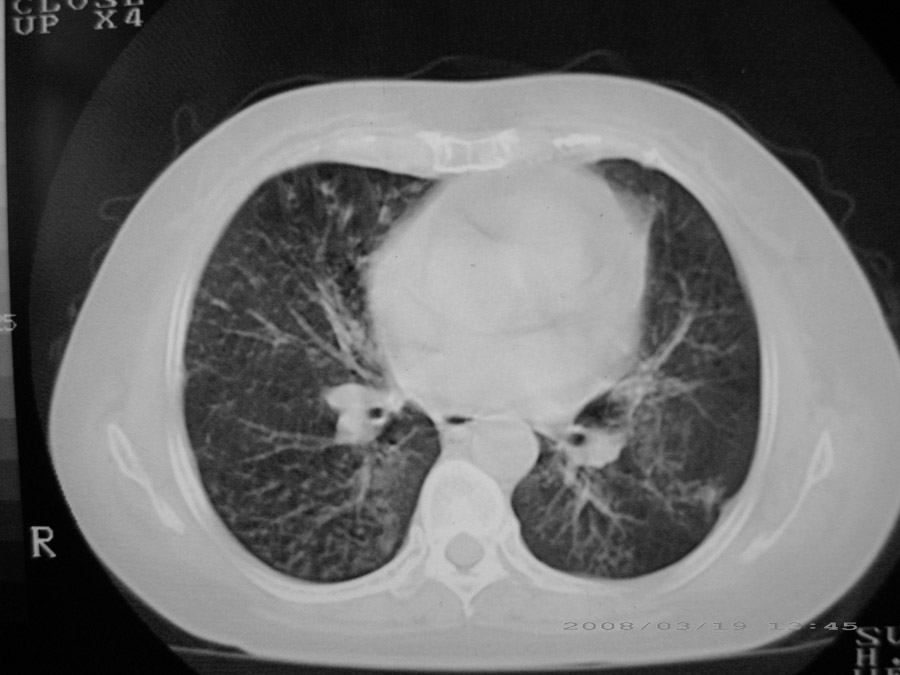

粟粒性结核

细支气管肺泡癌

本病例主要是癌性淋巴管炎与结节病的鉴别。好好查查吧。

密漫性沿纹理走行小结节影;有间质纤维化;可考虑尘肺;以图而论

血行播散性肺结核

两肺间质性病变!考虑间质纤维化?间质性肺炎!

双肺网状结构,小叶间质结节状增厚,考虑结节病

综合大家意见,结核、结节病、肺泡细胞癌均有可能,间质性肺炎暂不考虑,病灶纠集不明显,纵隔未见钙化淋巴结,尘肺可能性不大,但还是要密切结合临床诊断。

今天重新仔细看了看,矽肺确实不能除外,病灶主要表现为间质结节及纤维化。好好问问病史吧。